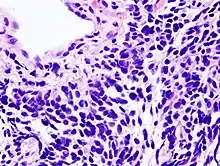

| Micrograph of a small-cell carcinoma of the lung showing cells with nuclear moulding, minimal amount of cytoplasm and stippled chromatin. FNA specimen. Field stain. | |

Small-cell carcinoma is an undifferentiated neoplasm composed of primitive-appearing cells. As the name implies, the cells in small-cell carcinomas are smaller than normal cells, and barely have room for any cytoplasm. Some researchers identify this as a failure in the mechanism that controls the size of the cells.[33]